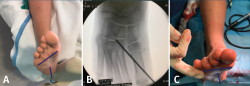

El calcáneo stop es un procedimiento mínimamente invasivo que consiste en limitar la RE-valgo del BCP y, por tanto, la subluxación del astrágalo en medial(12). Se hace mediante reducción en varo y colocación de un tornillo en el surco del calcáneo (fondo del ángulo de Gissane), cuya cabeza crea impingement con el proceso lateral del astrágalo en valgo (Figura 11).

Figura 11. Técnica de calcáneo stop. A: mínima incisión (1,5 cm), liberación del seno del tarso; B y C: colocación de aguja de Kirschner en el surco del calcáneo delante de la parte anterior del proceso lateral del astrágalo, con el pie en varo; D: posición de la cabeza del tornillo que hace impingement con el proceso lateral del astrágalo en valgo; E y F: imágenes radiológicas intraoperatorias, visualizando la orientación del tornillo de 30° en el plano sagital y 10° en el plano coronal.